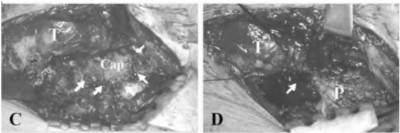

A 72-year-old female presents with progressive left thigh and knee pain for the last year. 5 years ago she sustained a femoral neck fracture treated with the implant seen in Figures A-C (current radiographs). The thigh pain is worse with weight-bearing. C-reactive

protein and erythrocyte sedimentation levels are within defined limits. Which of the following is the most likely cause of her pain?